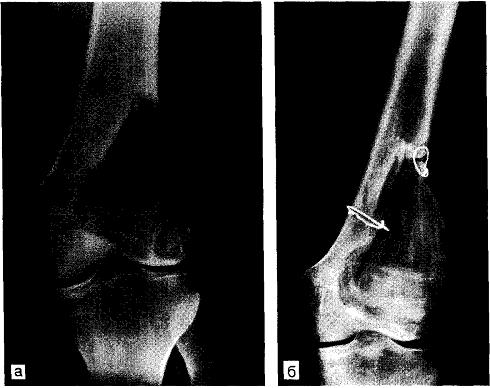

Литическая форма гигантоклеточной опухоли наружного мыщелка бедренной кости

Рентгенологически - возможно литическое поражение ячеистой структуры с чёткими границами; часто отсутствует склеротический ободок; очаг расположен субхондрально, эксцентрично; периостальная реакция отсутствует. Кортикальная пластинка может быть вздута, локально разрушена, наблюдается распространение опухоли в мягкие ткани.

Краевая резекция кости вместе с опухолью с пластикой дефекта. При локализации опухоли в области метаэпифизов производится так называемая околосуставная резекция, которая является разновидностью краевой резекции.